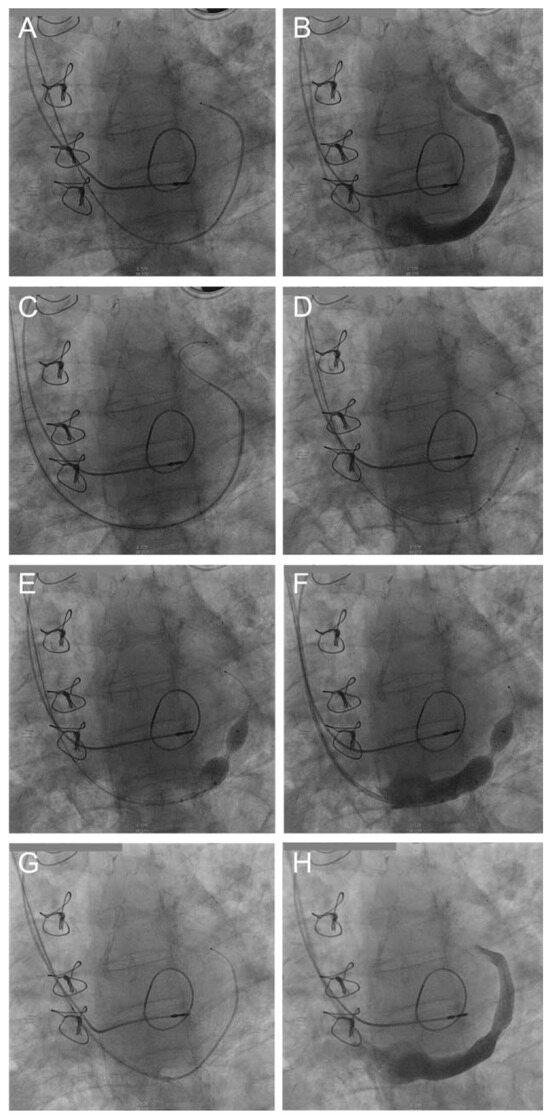

Familial hypercholesterolaemia: increasing physicians’ awareness in order to prevent early death. Familial hypercholesterolaemia (FH) is one of the most frequent autosomal dominant genetic conditions (1/200–300) and is still underdiagnosed and undert...